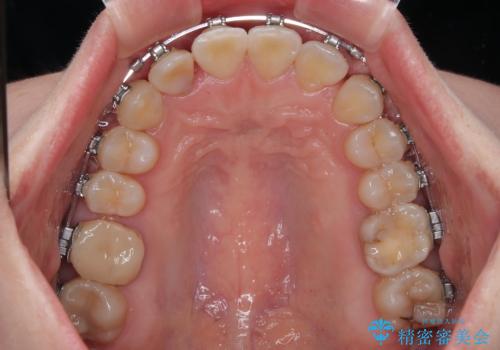

- 矯正装置

- メタルブラケット

マウスピースでもワイヤーでも対応可能でしたら、捻転が非常に強いことから、患者様と相談の上ワイヤー装置にて矯正治療を行うこととしました。

捻転を解消する際に、歯列全体が前方に突出して出っ歯の仕上がりとなることが懸念されたため、補助装置を用いて上顎歯列全体を後方に移動する力をかけることとしました。

当初予定通り1年半ほどの治療期間で、非常に綺麗な歯列に仕上げることができました。